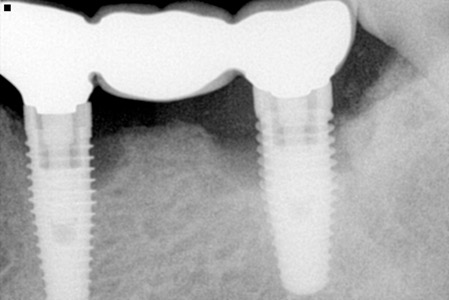

✔ 1️⃣ 利用「植牙牙橋」

例如缺 3 顆牙,不一定要 3 顆植體,

可以用 2 顆植體支撐 3 顆牙橋,安全又省,但前提是咬合力要輕、清潔要能徹底、無牙周疾病…等,始適用!(通常用於前牙)

👉 經過 X 光 / 3D 斷層檢查

👉 評估骨量、咬合、牙周

👉 計算受力 & 支撐,了解發生問題時的維修方式和困難

👉 尋找「對你來說最少、但仍然安全的植體數」